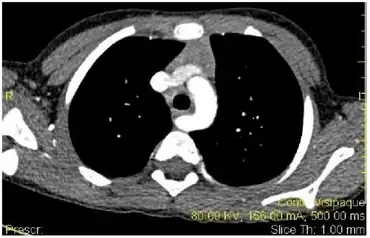

| Esophageal dysphagia- demonstrating the aberrant right subclavian artery compressing the esophagus. | |

- Aberrant subclavian artery, or (dysphagia lusoria)